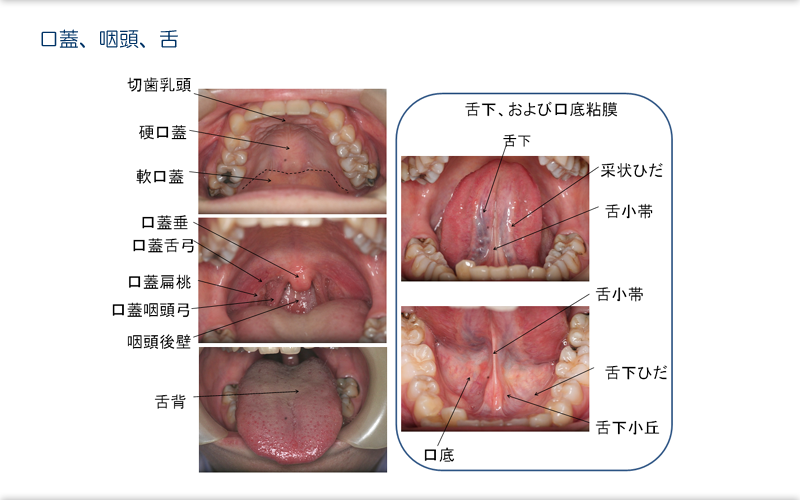

3.構造 解剖。

咽頭・喉頭の解剖用語ガストロ用語集 2023 「胃と腸」47巻5号より gastropedia ガストロペディア消化器にかかわる医療関係者のために。

舌について。

舌の仕組み。